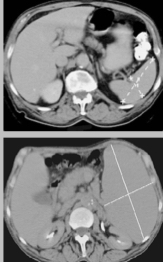

What is the structure of the spleen and where is it located?

Left side of abdomen, posterior to stomach, inferior to diaphragm.

What is splenomegaly?

Where the spleen enlarges in response to localised/systemic infection due to proliferation B-cells.

Can lead to rupturing and exsanguiation

What would you do with a ruptured spleen and why would you try to avoid it?

Splenectomy